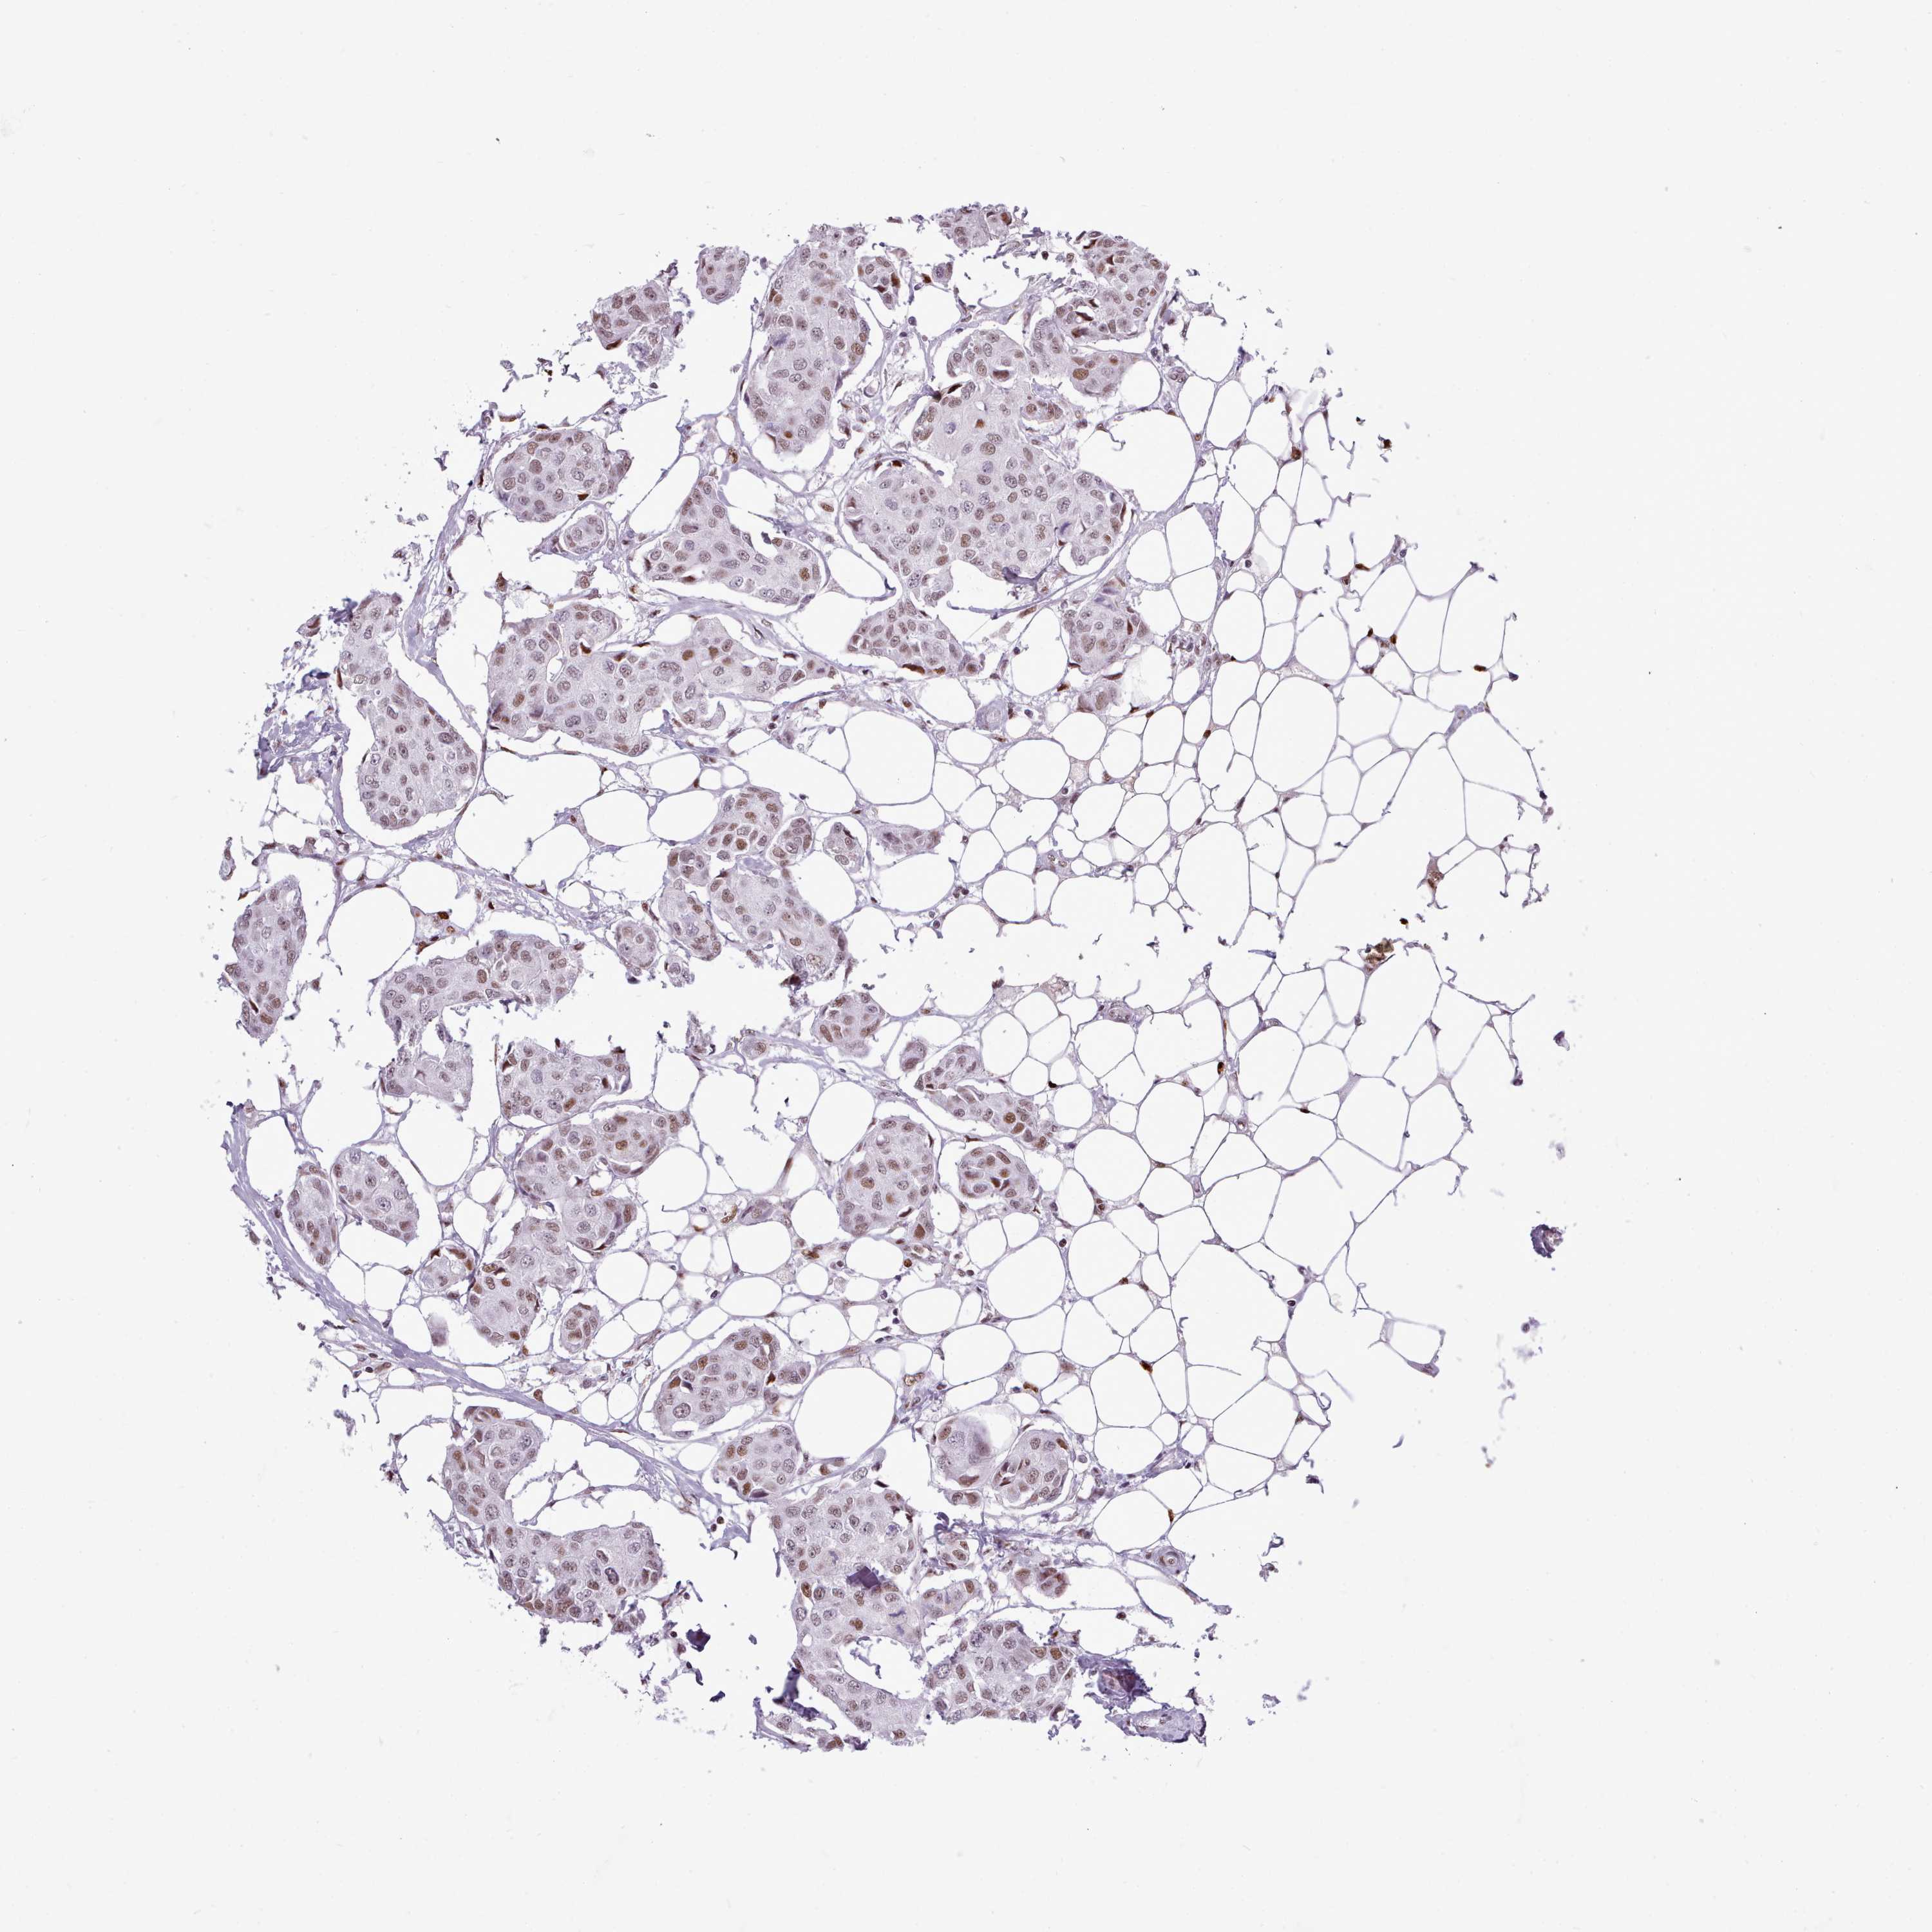

BRCA TCGA BRCA VALIDATION PROTEIN EXPRESSION

ANTIBODIES

AND

VALIDATION